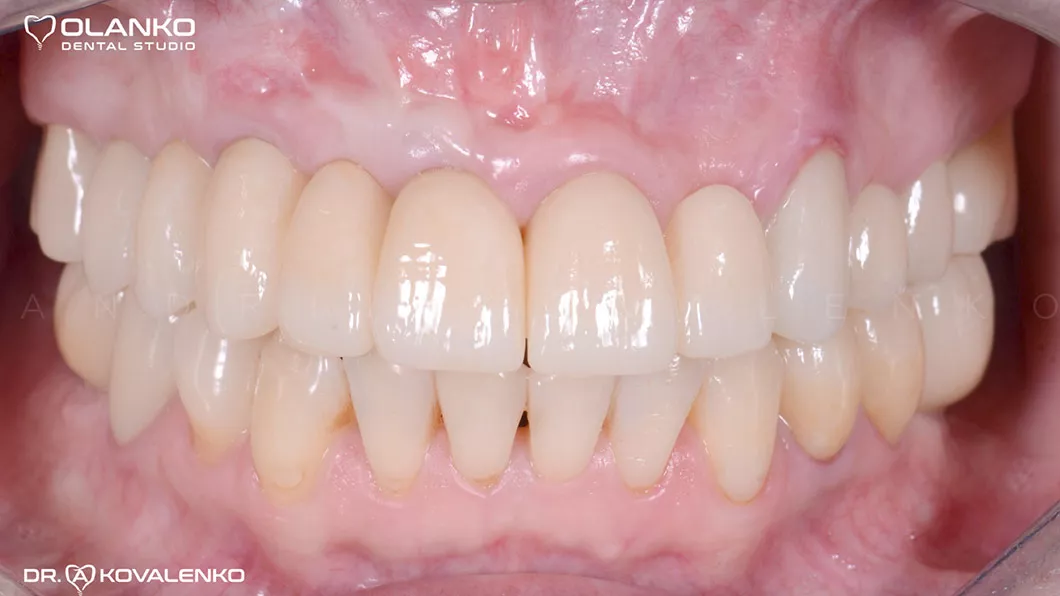

Вид после фиксации керамических конструкций

Протезирование: цельнокерамическими мостовидными протезами и коронками на зубах, имплантатах.